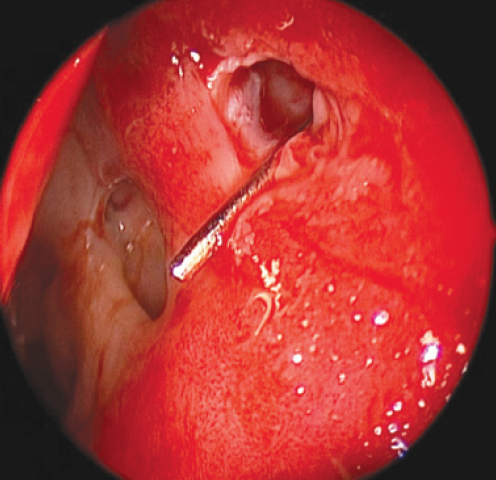

The intervention was performed as follows. Under local and conduction anesthesia with intravenous sedation, antegrade probing of the dacryostomy area was performed with the formation of an opening in the scar tissue (in three cases) and with probing of residual dacryostomy (in three cases; Fig. 2). Purulent discharge was removed from the lacrimal sac cavity using an aspirator. A balloon was inserted endonasally into the dacryostomy opening using a curved von Eicken cannula for irrigation with an outer diameter of 4.0 mm and length of 15 cm (Karl Storz, Germany; Fig. 3). Balloon dacryoplasty was performed according to the protocol we developed earlier in the experiment [8] and tested in the clinical setting (Fig. 4) [9]. The balloon was dilated at a pressure of 8 atm. for 90 s, and after 10 s, it was repeated for 60 s. After deflation, the balloon was removed. Figure 5 shows an enlarged dacryostomy after the intervention. A hemostatic sponge was inserted into the dacryostomy area, which was removed 48 h after the surgery.

Fig. 2. Endoscopic view of scar tissue in the area of dacryostoma (left nasal cavity). The ostium was probed with Bowman probe

Рис. 2. Эндоскопическая картина области рубцово-изменнённой дакриостомы (левая половина носа). Зонд Боумена выведен через дакриостому